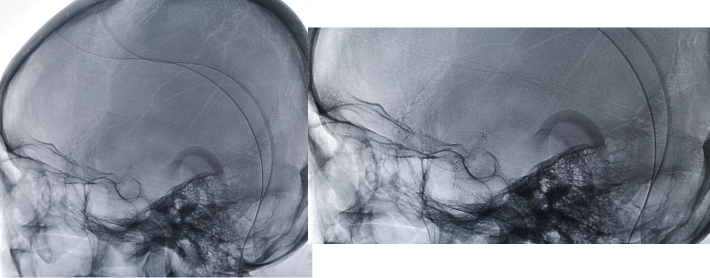

微导丝通过狭窄血管段

放置微导丝远端至左侧大脑中动脉上干M2段

3mm*15mm球囊扩张

球囊扩张后

4.5mm*22mm Enterprise 支架

术 后

✔支架选择:左侧颈内动脉虹吸段狭窄段长度较长,远端至左侧大脑中动脉M1起始段,近端至眼动脉开口上方。且此段血管迂曲,狭窄段近端、远端都有较大的血管转折,使用球扩支架风险很高。因此我们选用了顺应性较好,又有一定支撑力的自膨支架——Enterprise 支架。

✔术中要点:左侧颈内动脉虹吸段狭窄考虑为夹层,予反复多个角度导引导管造影,以明确真假血管腔,微导丝通过狭窄段血管时谨慎、轻柔操作,务必判断导丝应从真腔通过。先予球囊扩张,观察扩张后狭窄段血管管径恢复情况。释放前准确定位支架近端,远端,应完全覆盖狭窄血管段。